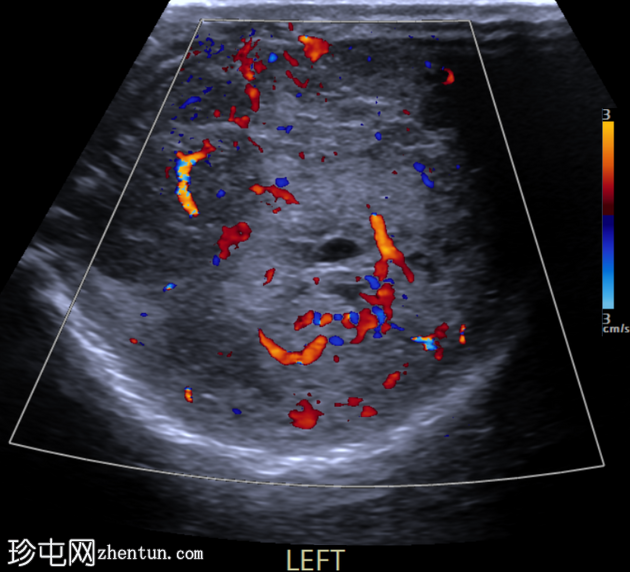

左侧睾丸可见边界不清的肿块,实质回声不均匀,并可见囊性区域。彩色多普勒超声显示血流信号增多。未见钙化。